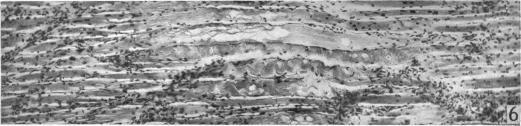

An experimental study of the regeneration of mammalian striped muscle.

摘要